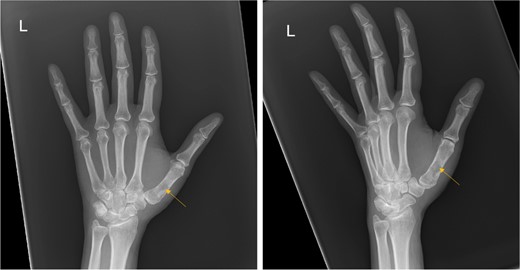

X-ray showed a well-defined non-aggressive lytic bony lesion of the first metacarpal bone (Fig. 1). Magnetic resonance imaging (MRI) showed a grossly stable skin and subcutaneous multilobulated soft tissue mass located at the palmar aspect of the wrist joint measuring 6 × 2 × 3.3 cm3 in its maximum anteroposterior, transverse and craniocaudal dimensions, respectively (Figs 2 and 3). The lesion showed low and high signals in T1 - and T2-weighted images with homogenous contrast enhancement. The lesion was inseparable from the flexor carpi radialis and palmaris longus tendons without definite invasion or encasement. The lesion was not in continuity, however, with the serpiginous lytic bony lesion noted at the first metacarpal bone exhibiting low T1 and high T2 signals with peripheral enhancement and no cortical destruction or associated soft tissue component (Fig. 4).

MRI of the left distal forearm showing cutaneous and subcutaneous lobulated mass at the volar aspect of high T2 and low T1 signals with diffuse enhancement. (A) Coronal T2-weighted fat saturated image. (B) Axial T2-weighted fat saturated image. (C) Axial T1-weighted image. (D) Axial T1-weighted fat saturated image post gadolinium injection.